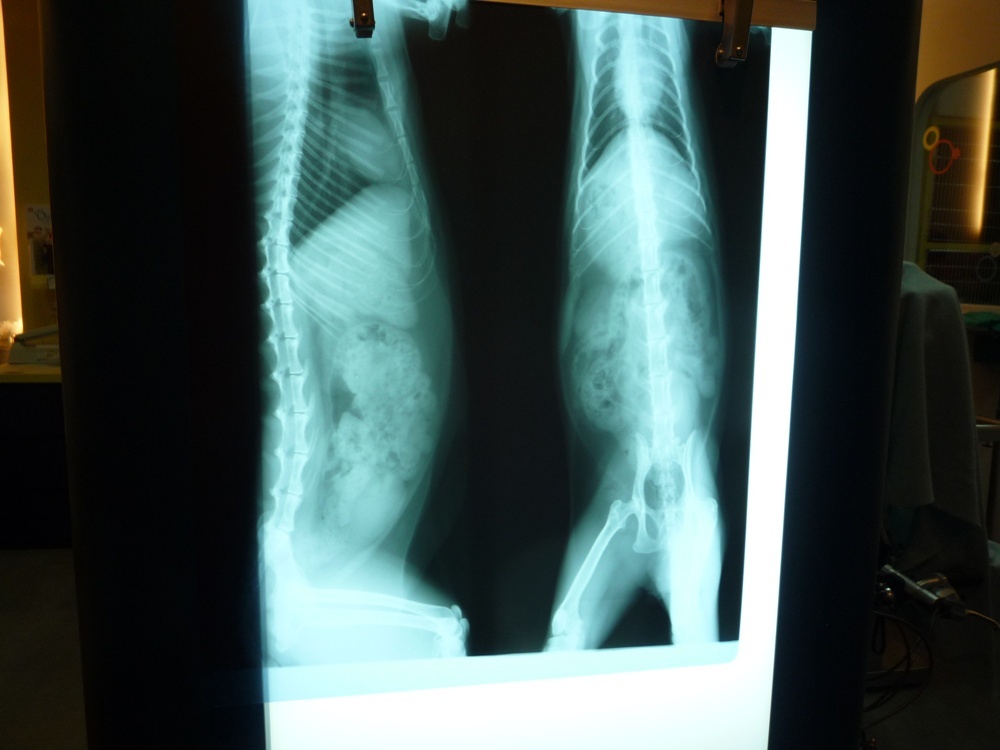

主題: 蹲在路邊尿尿有問題~ 申請者姓名: 陳曉霏 花色: 申請日期: 2012-10-26 01:51:03 申請者部落格: 申請者臉書網址: http://www.facebook.com/xiaofeic 所在縣市/合作醫院: 台北市/長沁動物醫院 治療費用: 5120元 需求人數: 7人 已結案 (2013-07-09 13:52:07) 報名人員: Lisa Cheng(已付款)、Lisa Cheng、Lisa Cheng、黃台芸、黃台芸、張雅筑(已付款)、Lulu Nova、陳小可(已付款)、周星星(已付款)、陳可可(已付款)、Ivy Chen(已付款)、Tiffany Shen(已付款)、 候補人員: 動物病情說明: 疑似走失的孩子

非常的親人

發現他時 正用著奇怪的姿勢蹲著想尿尿

但卻尿不出來!

餵他吃東西 他吃了就吐@@

醫生檢查後 發現他白血球偏高

還是一個愛滋的孩子~

尿濃度也很高

經過醫生細心的照顧下

目前狀況已經穩定